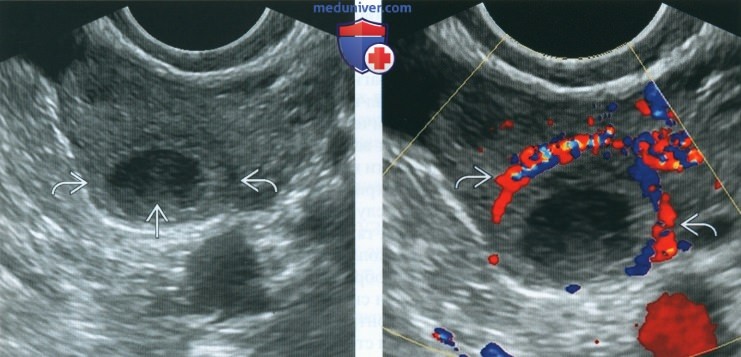

Гистологические изображения фолликулярной кисты яичника